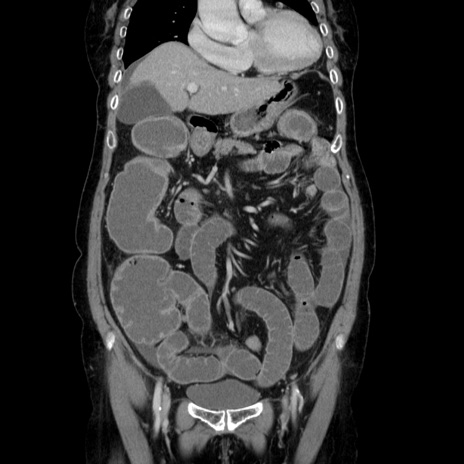

症例5(冠状断像)

【症例】70歳代女性

【主訴】お腹が張る

【現病歴】1週間くらい前から腹部膨満の自覚あり。昨日夜から増悪したため、本日救急外来受診。

【身体所見】意識清明、BT 36.5℃、BP 165/106mmHg、HR 80bpm、SpO2 98%、腹部:膨満、軟、自発痛・圧痛なし、触診にて不快感あり、腸蠕動音:減弱

【データ】WBC 12600、CRP 1.04